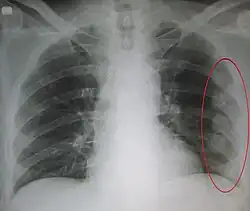

Since most causes of pediatric and adolescent chest pain are not considered life-threatening, parents and their children are often reassured that in the majority of cases, the cause of the pain can be determined. If the child or adolescent appears to have some dehydration, and intravenous line along with administration of saline is done. The clinician may or may not decide to perform diagnostic testing . This is especially true if the child or adolescent has symptoms of chronic pain. If an obvious cause of the chest pain is not readily apparent, testing may begin with an x-ray and an electrocardiogram . This helps the clinician to determine whether or not the cause of pain is related to pulmonary or cardiac causes.[4]

- pleural effusion and chest pain may be related to arthritis

- Pleural effusion[1]

- Pleural effusion[4]

- Pneumothorax